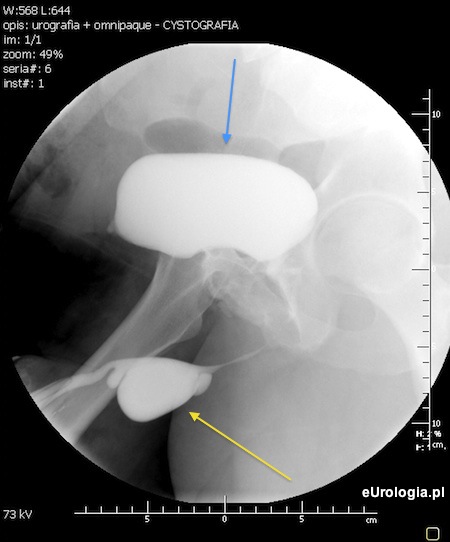

Fot. Uretrografia przedstawiająca uchyłek cewki moczowej - żółta strzałka. Strzałka niebieska przedstawia pęcherz moczowy wypełniony kontrastem.